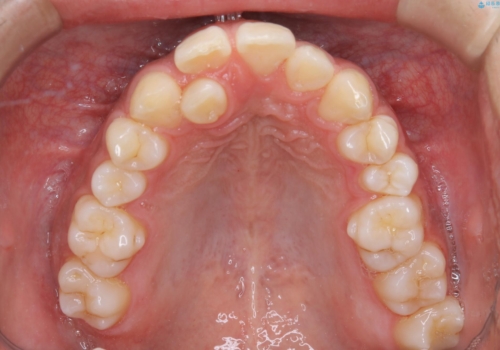

矯正をスタートする前にクリーニングを行いました。PMTC60分コースを行いました。

10年ぶりのクリーニングのため着色や歯石、プラークの量は多めでした。